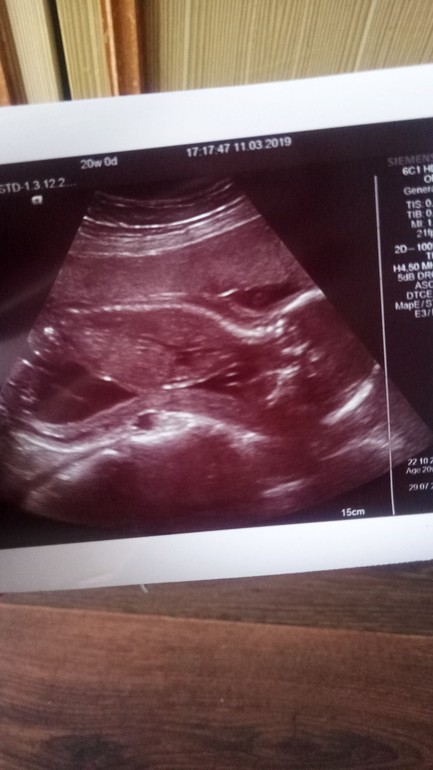

IT'S A BOOOY

Вчера нам было ровно 20 недель. Был скрининг. Боялась очень, понимала что надо успокоиться, ведь на первом скрининге в общих чертах все было норм. Но наверное каждая будущая мама боиться и волнуется перед скринингом. Ну вобщем все у нас хорошо, с органами, с конечностями, с губкой )) Мы растем и развиваемся как положено. И еще новость, у нас будет мальчик!!! Будет полный набор, Ритульке моей братишка!) Лежал личиком к позвоночнику и кадр у нас получился вот такой)))Ура ура ура!!